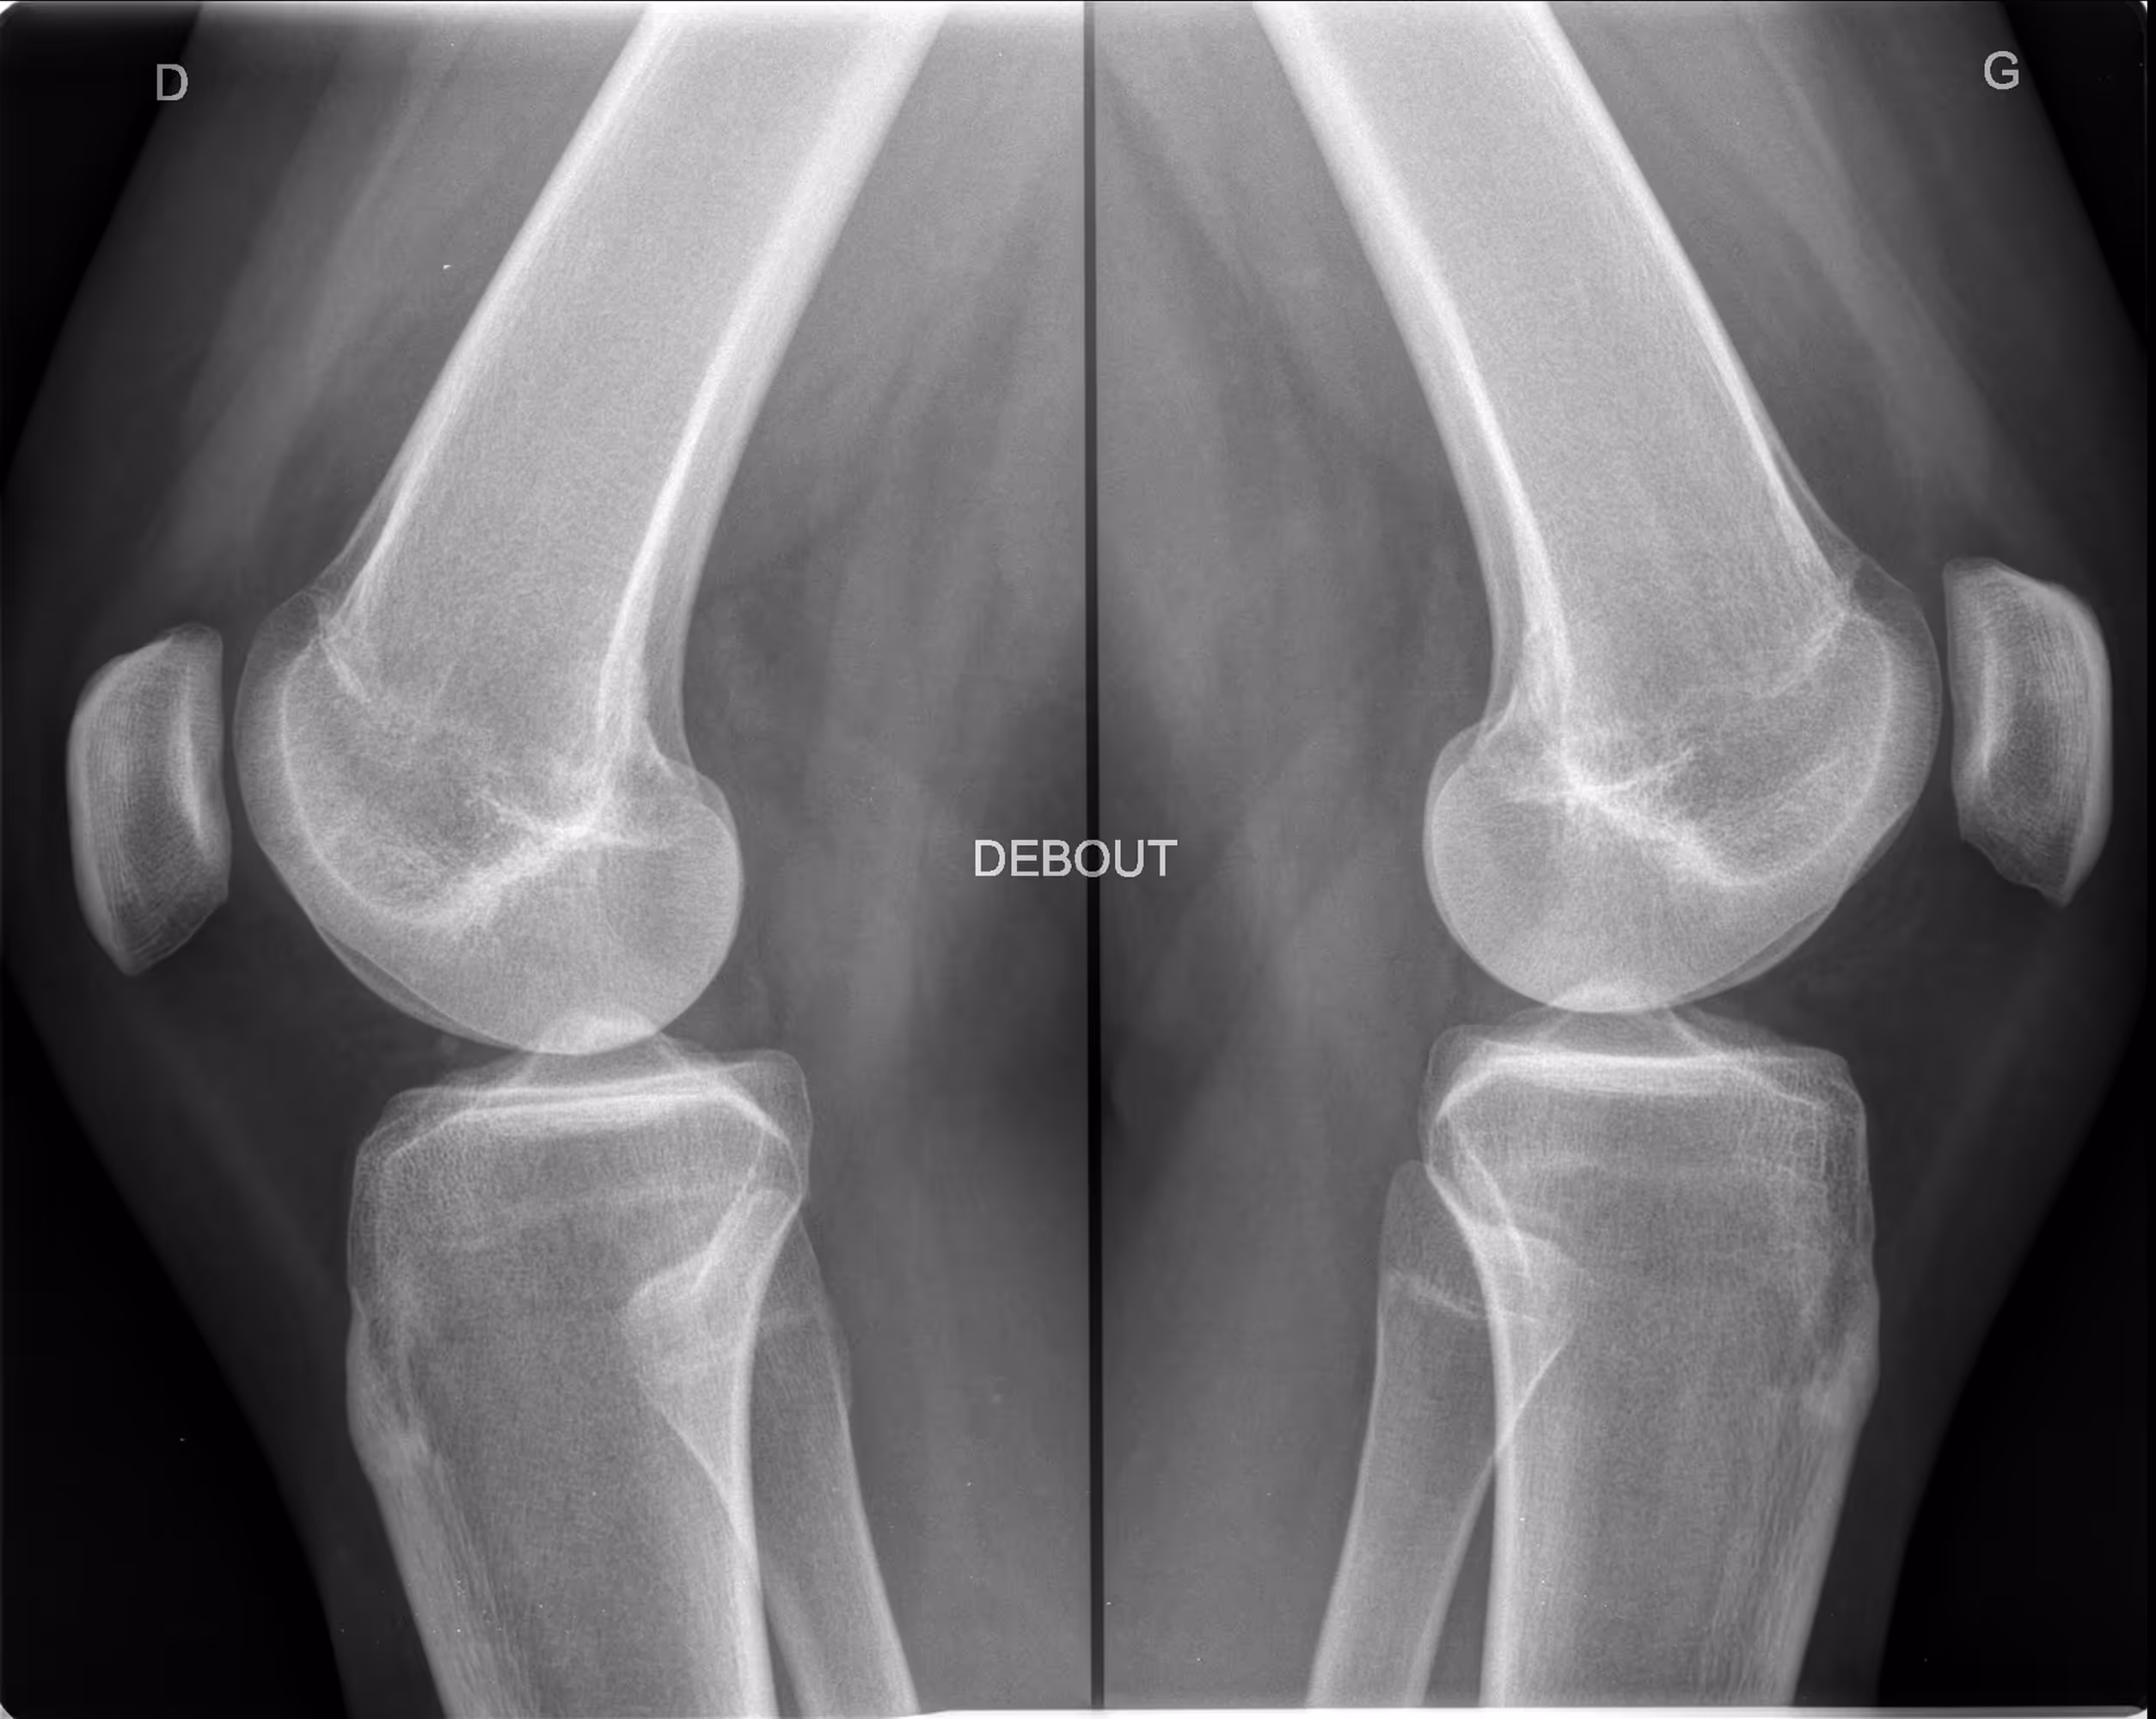

This is the defA 45-year-old female presenting with foot discomfort and difficulty wearing shoes.ault title value

BoneMetrics detected a bilateral hallux valgus, with greater deformity on the left side.